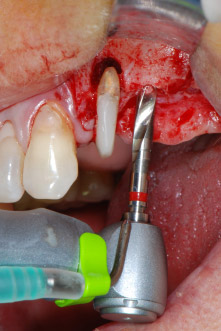

IImplant beds were prepared at sites 25 and 26 with rotary instruments, used in a contra-angle handpiece with a 20 : 1 transmission ratio with an updated powerful implant motor (Implantmed, W&H) (Fig. 8).

The final preparation next to the sinus was again carried out with a piezoelectric instrument (Piezomed, insert S2).